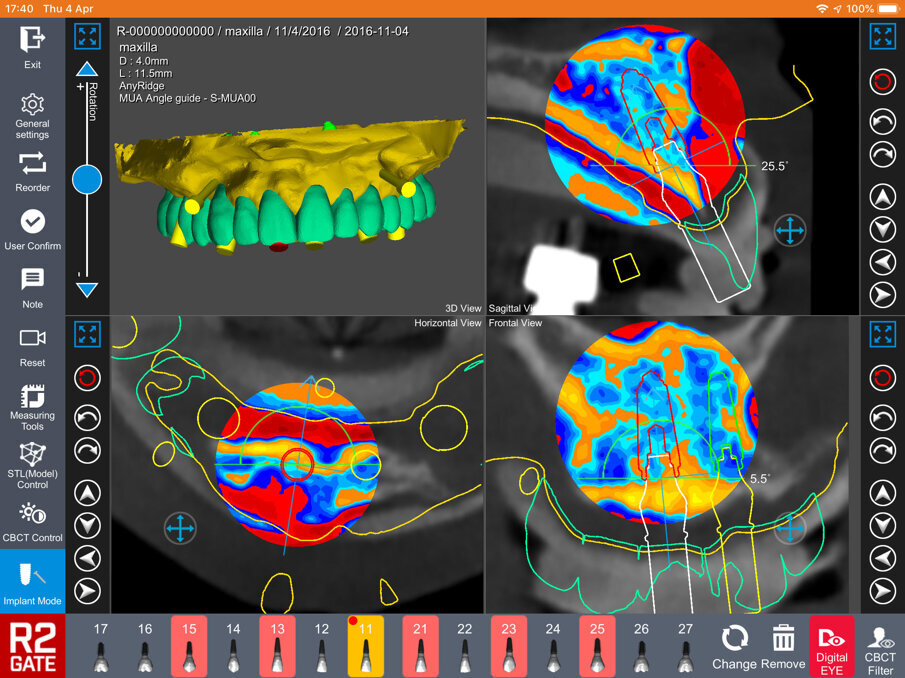

Il sistema prevede la scannerizzazione della protesi totale provvisoria che viene accoppiata con la CBCT del paziente e produce un “modello” di studio nel quale il clinico può non solo pianificare la chirurgia implantare ma anche selezionare la tipologia di fixture da inserire e il tipo di abutment protesico da connettere agli impianti (Fig. 4a). Il software R2Gate consente di posizionare tridimensionalmente gli impianti nel rispetto dell’anatomia locale e della qualità dell’osso presente (Fig. 4b). Uni dei grandi vantaggi di questo software è di contenere una funzione chiamata “digital eye” una porzione di software che valuta la qualità dell’osso utilizzando una scala colori e fornendo al clinico utilissime informazioni a riguardo del tipo di preparazione del sito e alla sequenza di frese da utilizzare in funzione della qualità stessa (Fig. 4c). Questo tipo di progettazione associata alla ricerca non solo dei siti ma anche della qualità dell’osso consente di prevedere con una alta approssimazione la possibilità di ottenere una buona stabilità primaria degli impianti ed in conseguenza di poter pianificare un carico immediato.